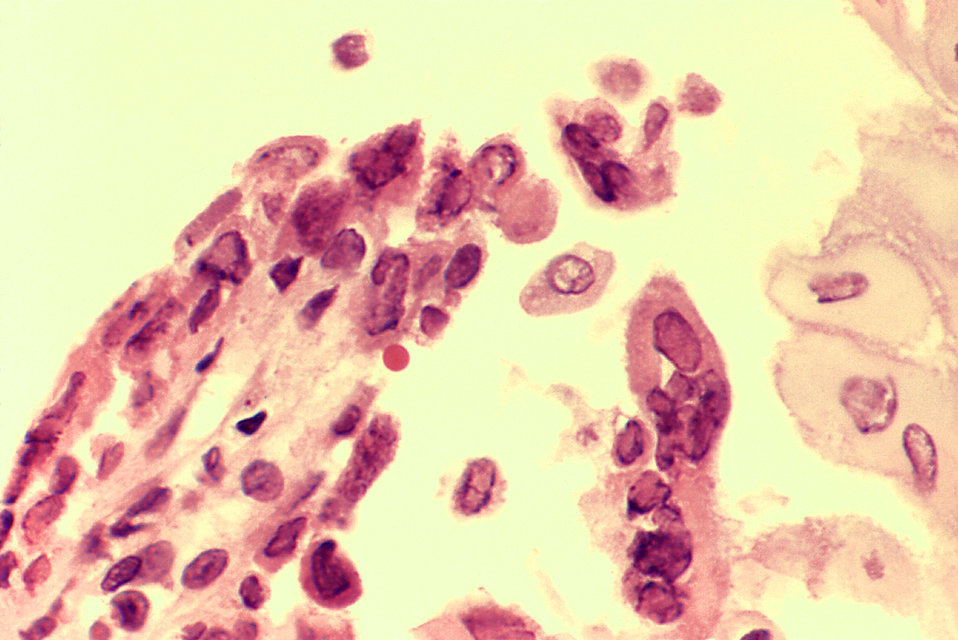

Shedding occurs when herpes successfully reproduces and leaves the host cell, whereby it could potentially infect another person. The process can occur without any noticeable symptoms. This — combined with the fact that the herpes simplex virus cleverly conceals itself in the central nervous system where the immune system can’t eradicate it — helps explain why about two-thirds of people worldwide have some form of herpes.

Although researchers are searching for a cure, none currently exists for the eight strains of herpes virus, which include chicken pox and shingles, in addition to what’s commonly called oral (HSV-1) and genital (HSV-2) herpes.